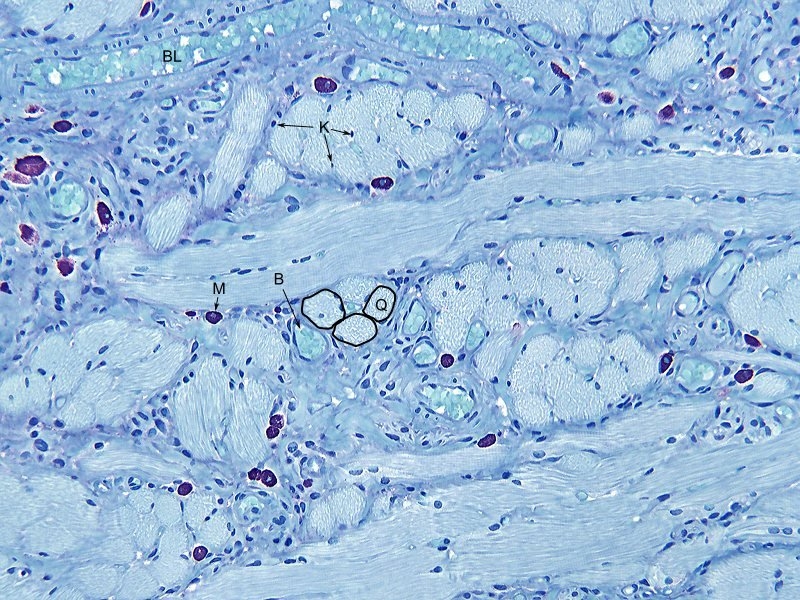

L= Muskelzelle Längs getroffen

Q= Muskelzelle Quer getroffen

B= Blutgefäß Quer getroffen

BL= Blutgefäß Längs getroffen

M= Mastzelle

K= Kernen von Muskelzellen

Objektiv, Leitz Plan Fluotar 16x